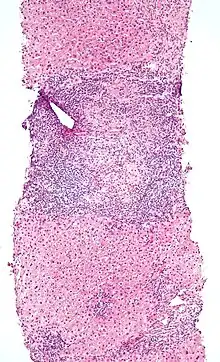

Low magnification micrograph of PBC. H&E stain. -

On microscopic examination of liver biopsy specimens, PBC is characterized by chronic, non-suppurative inflammation, which surrounds and destroys interlobular and septal bile ducts. These histopathologic findings in primary biliary cholangitis include the following:[34]

- Inflammation of the bile ducts, characterized by intraepithelial lymphocytes, and

- Periductal epithelioid granulomata.

- Proliferation of bile ductules

- Fibrosis (scarring)

The Ludwig and Scheuer scoring systems have historically been used to stratify four (1–4) ‘stages’ of PBC, with stage 4 indicating the presence of cirrhosis. In the new system of Nakanuma, the stage of disease is based on fibrosis, bile duct loss and features of cholate-stasis, i.e. deposition of orcein-positive granules, whereas the grade of necroinflammatory activity is based on cholangitis and interface hepatitis. The accumulation of orcein-positive granules occurs evenly across the PBC liver, which means that staging using the Nakanuma system is more reliable regarding sampling variability.